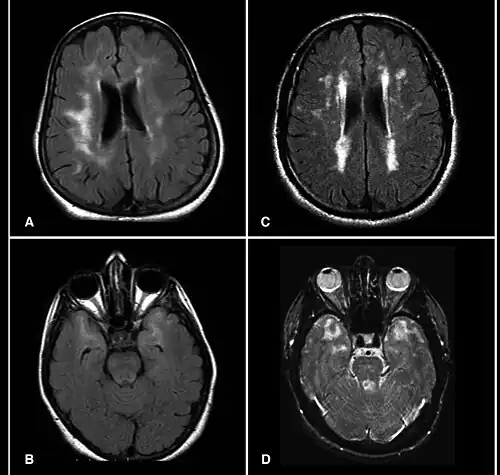

Brain MRI from patients with CADASIL showing multiple lesions. | |

MRIs show hypointensities on T1-weighted images and hyperintensities on T2-weighted images, usually multiple confluent white matter lesions of various sizes, are characteristic. These lesions are concentrated around the basal ganglia, peri-ventricular white matter and the pons and are similar to those seen in Binswanger disease.[2][11] These white matter lesions are also seen in asymptomatic individuals with the mutated gene.[12] While MRI is not used to diagnose CADASIL, it can show the progression of white matter changes even decades before onset of symptoms.